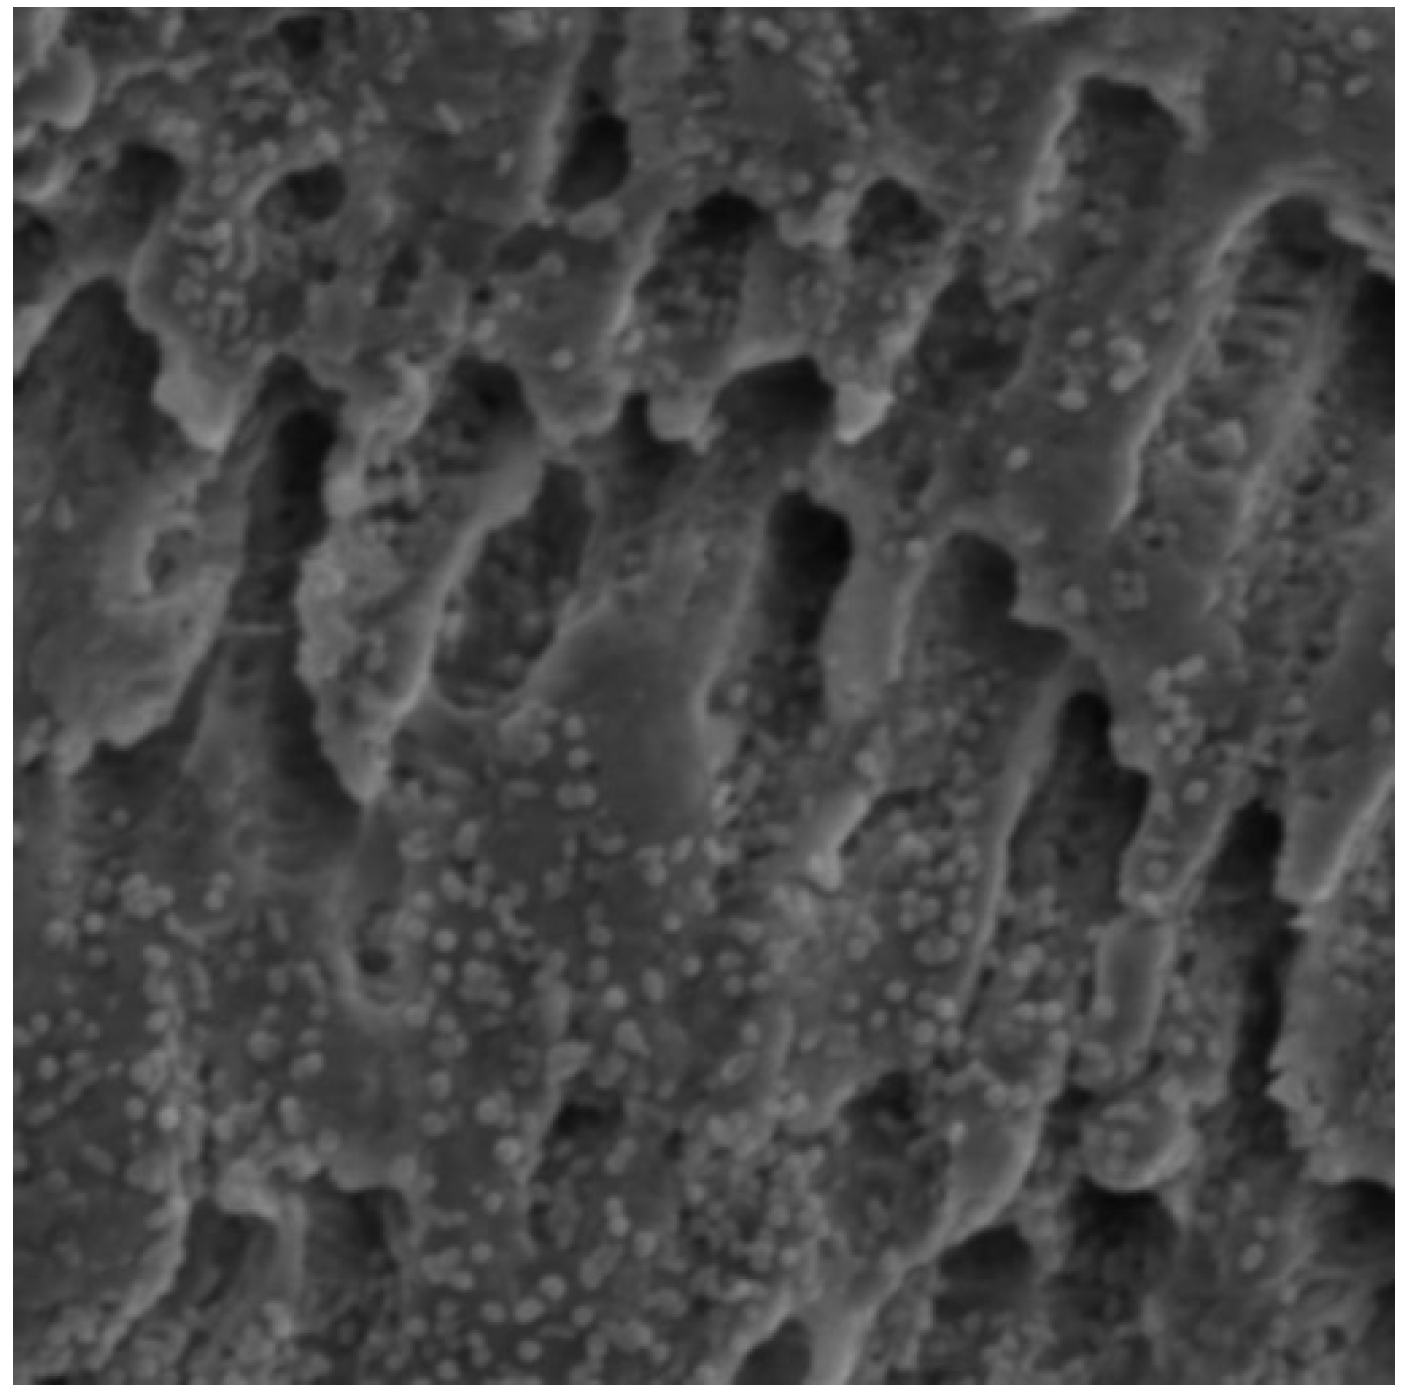

3.2. Qualitative Results of Scanning Electron Microscopy and Confocal Laser Scanning Microscopy